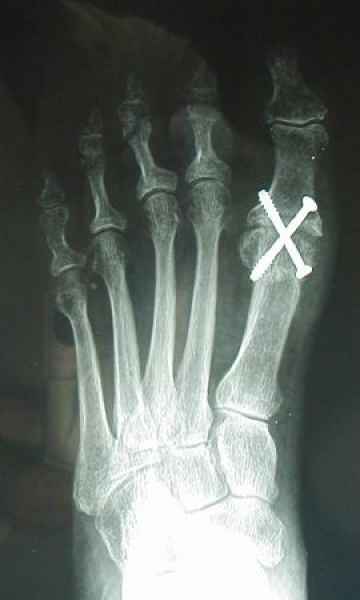

La marcha no solo es característica de la especie humana sino también de cada persona, y más aún varía según el estado de ánimo del momento. Una patología en los pies, se traduce en el rostro, en el ánimo, en el psiquismo. No sólo el dolor produce estos efectos, también un pie deformado o poco estético. En nuestra sociedad, la estética constituye un valor muy apreciado y estas alteraciones causan vergüenza fundamentalmente en las mujeres, que esconden en la playa sus pies en la arena y no pueden usar calzados elegantes.

Tanto la estructura del pie como su funcionalismo que es la marcha, pueden ser asiento y manifestación respectivamente de alteraciones locales ó sistémicas, por lo que su cuidadoso examen resulta de extrema utilidad diagnóstica.